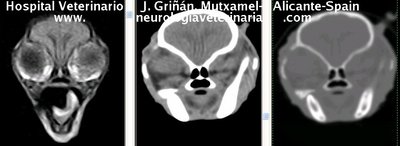

Se muestran cortes transversales de Resonancia Magnética (imagen a la izqda del lector), TC contrastado para tejidos blandos (imagen del centro) y TC contrastado para tejidos duros (imagen de la derecha del lector).

Nótese como la Resonancia supera al TC en el contraste de tejidos blandos (encéfalo y médula espinal) y en el de líquidos (ojo y líquido cefalorraquídeo), mientras que el TC supera a la resonancia en el contraste de tejidos duros (hueso) y aire (senos, cavidad nasal y bullas)

Cortes a nivel de los lóbulos cerebrales frontales